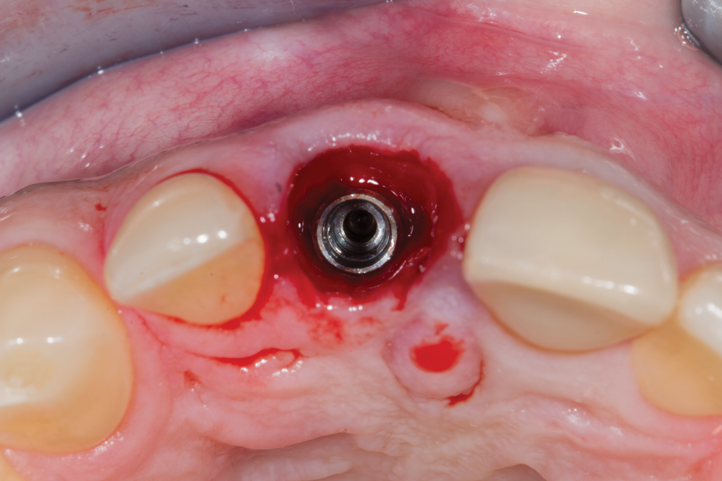

Fig 13. Anatomically correct composite-customized healing abutment immediately affixed to implant at implant placement to provide long-term physical support for the mucosal tissues.

Figure 13